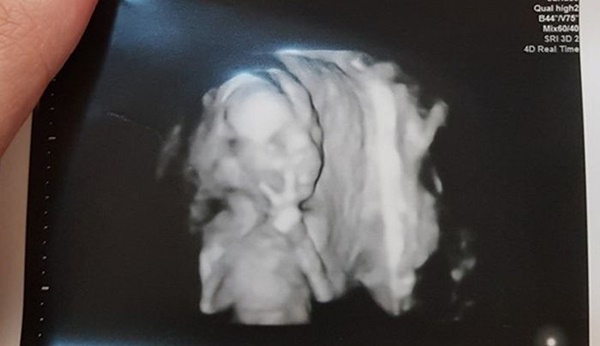

Vào ngày 31/5 vừa qua, một ông bố ở Đài Loan đăng lên Facebook ảnh chụp siêu âm của con với dòng caption: "Con tôi chào mọi người đây, tôi tò mò không biết những đứa trẻ khác có như vậy không?" và thu hút sự chú ý của đông đảo dân mạng. Theo đó, đứa trẻ này dường như biết được bác sĩ đang chụp hình siêu âm 3D nên đã giơ tay vẫy chào, miệng có vẻ cũng mỉm cười. Sau đó, đứa trẻ tinh nghịch này còn chuyển sang giơ tay chữ V. Bác sĩ cũng cho biết đây là lần đầu tiên họ nhìn thấy đứa trẻ hành xử như vậy trong lúc chụp hình siêu âm.